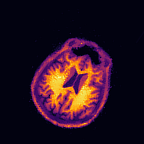

Multi-modality (or multi-channel) imaging is becoming increasingly important and more widely available, e.g. hyperspectral imaging in remote sensing, spectral CT in material sciences as well as multi-contrast MRI and PET-MR in medicine. Research in the last decades resulted in a plethora of mathematical methods to combine data from several modalities. State-of-the-art methods, often formulated as variational regularization, have shown to significantly improve image reconstruction both quantitatively and qualitatively. Almost all of these models rely on the assumption that the modalities are perfectly registered, which is not the case in most real world applications. We propose a variational framework which jointly performs reconstruction and registration, thereby overcoming this hurdle. Numerical results on simulated and real data show the potential of the proposed strategy for various applications in multi-contrast MRI, PET-MR, and hyperspectral imaging: typical misalignments between modalities such as rotations, translations, zooms can be effectively corrected during the reconstruction process. Therefore the proposed framework allows the robust exploitation of shared information across multiple modalities under real conditions.